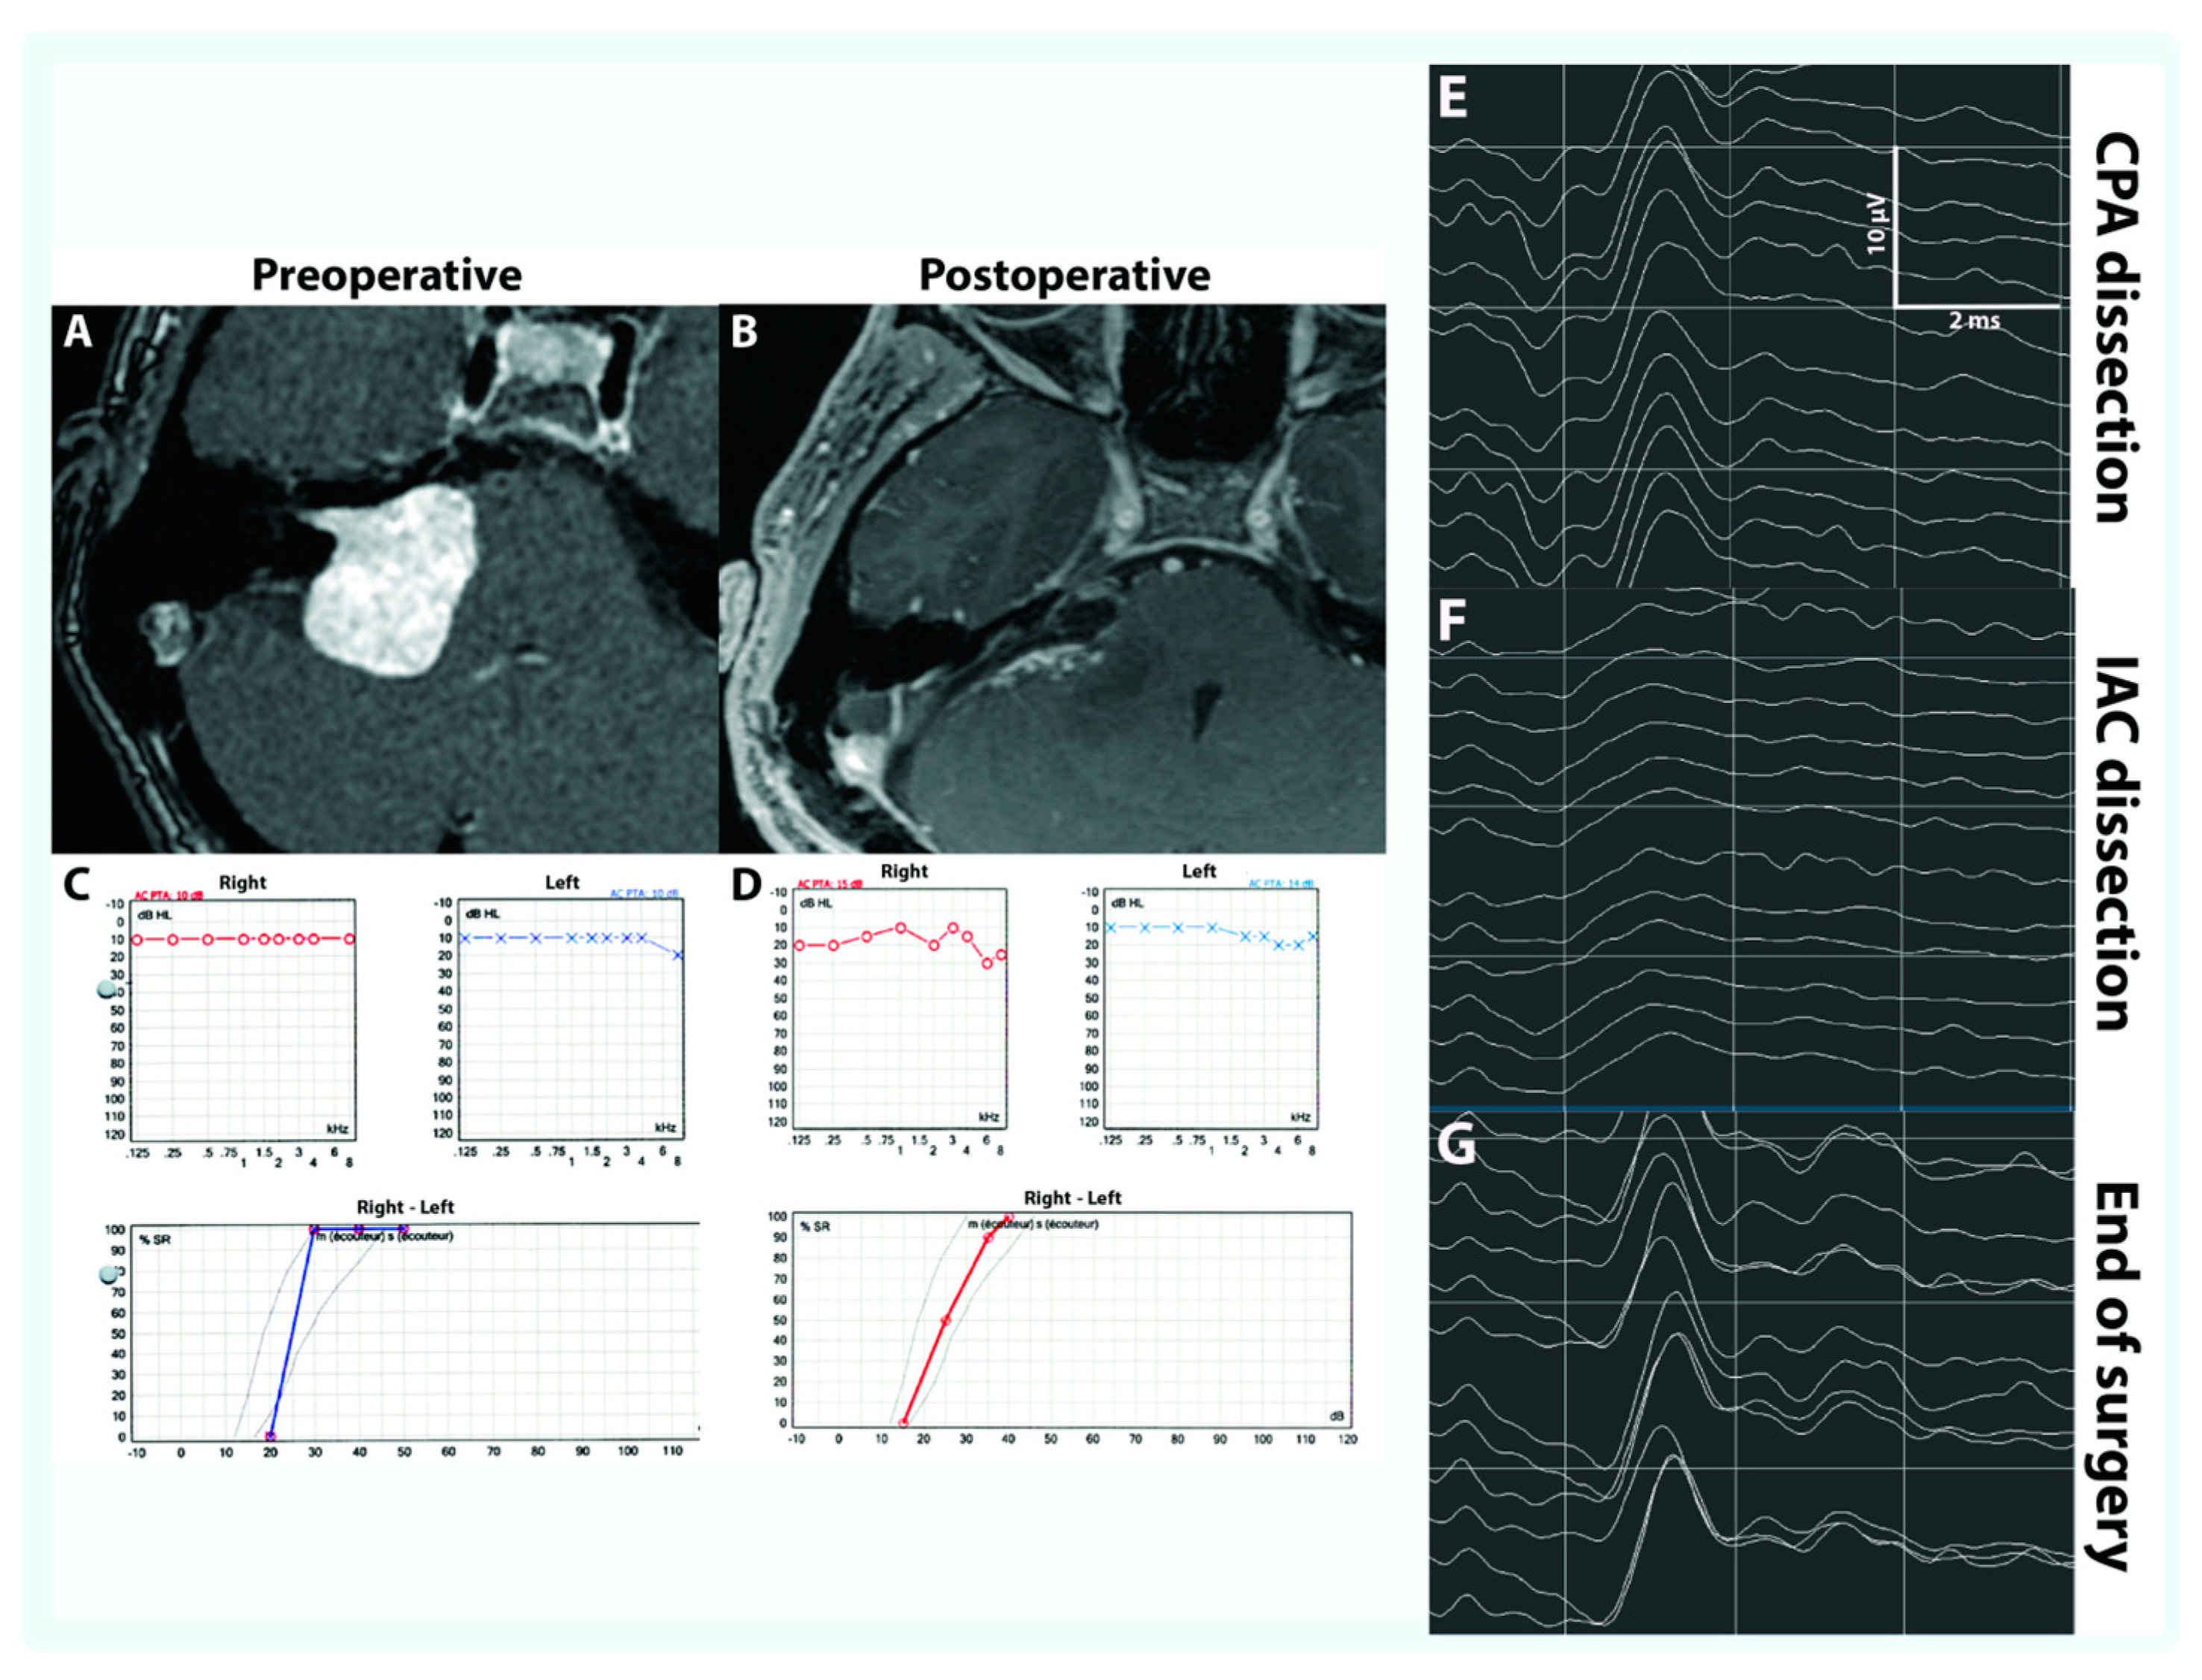

3.1. CNAP

3.3. Hearing Preservation